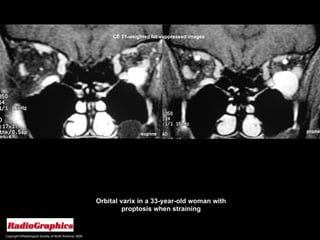

Copyright ©Radiological Society of North America, 2008 Orbital varix in a 33-year-old woman with proptosis when straining prone supine CE T1-weighted fat-suppressed images